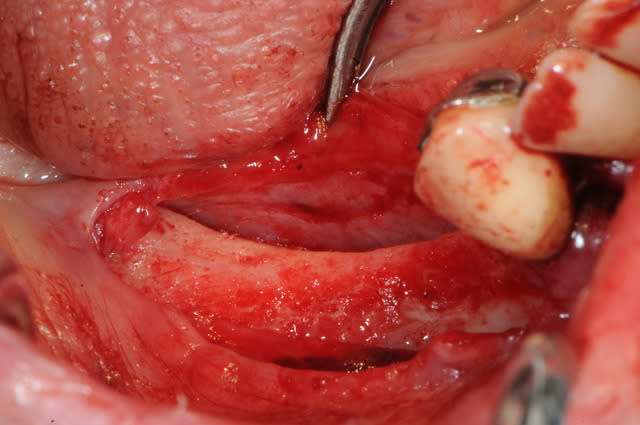

voici peut être une autre solution qui te satisfera d'avantage car beaucoup plus simple à mettre en œuvre.

c'est une simple ROG avec des vis pour maintenir l'espace sous la membrane.

Dsc 4158 dklw1n - Eugenol

tu as utilisé le ballonnet pour obtenir la laxité de la muqueuse ?

oups ! j'avais oublié les opt

merci à ceux qui ont déja pratiqué cette technique de me dire quel est leur mode opératoire. les résultats, les p'tits trucs pour faire avancer la science quoi ...